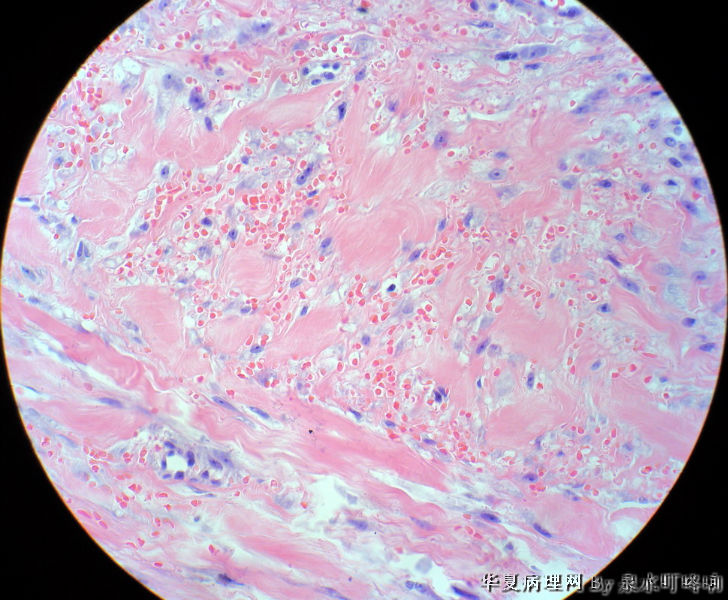

男,49岁,左肩胛部肿物。

图3